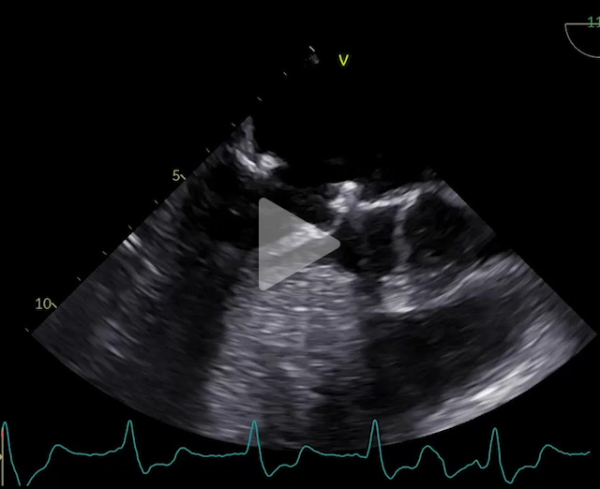

Voici son échocardiographie

Vidéo 1 : échocardiographie 2D en incidence parasternale grand axe

Vidéo 2 : échocardiographie 2D en incidence parasternale grand axe avec doppler couleur

- Patient de 40 ans avec une CMH sarcomérique (mutation HTZ MYBPC3) avec épaisseur maximale en antéro-septo-basal à 33mm en IRM, associée à une obstruction sous aortique significative (GD max 77 mm Hg au Valsalva). Découverte d’une insuffisance mitrale (IM) sévère mixte organique sur prolapsus de P2 et fonctionnelle sur un SAM (mouvement systolique antérieur de la valve mitrale)